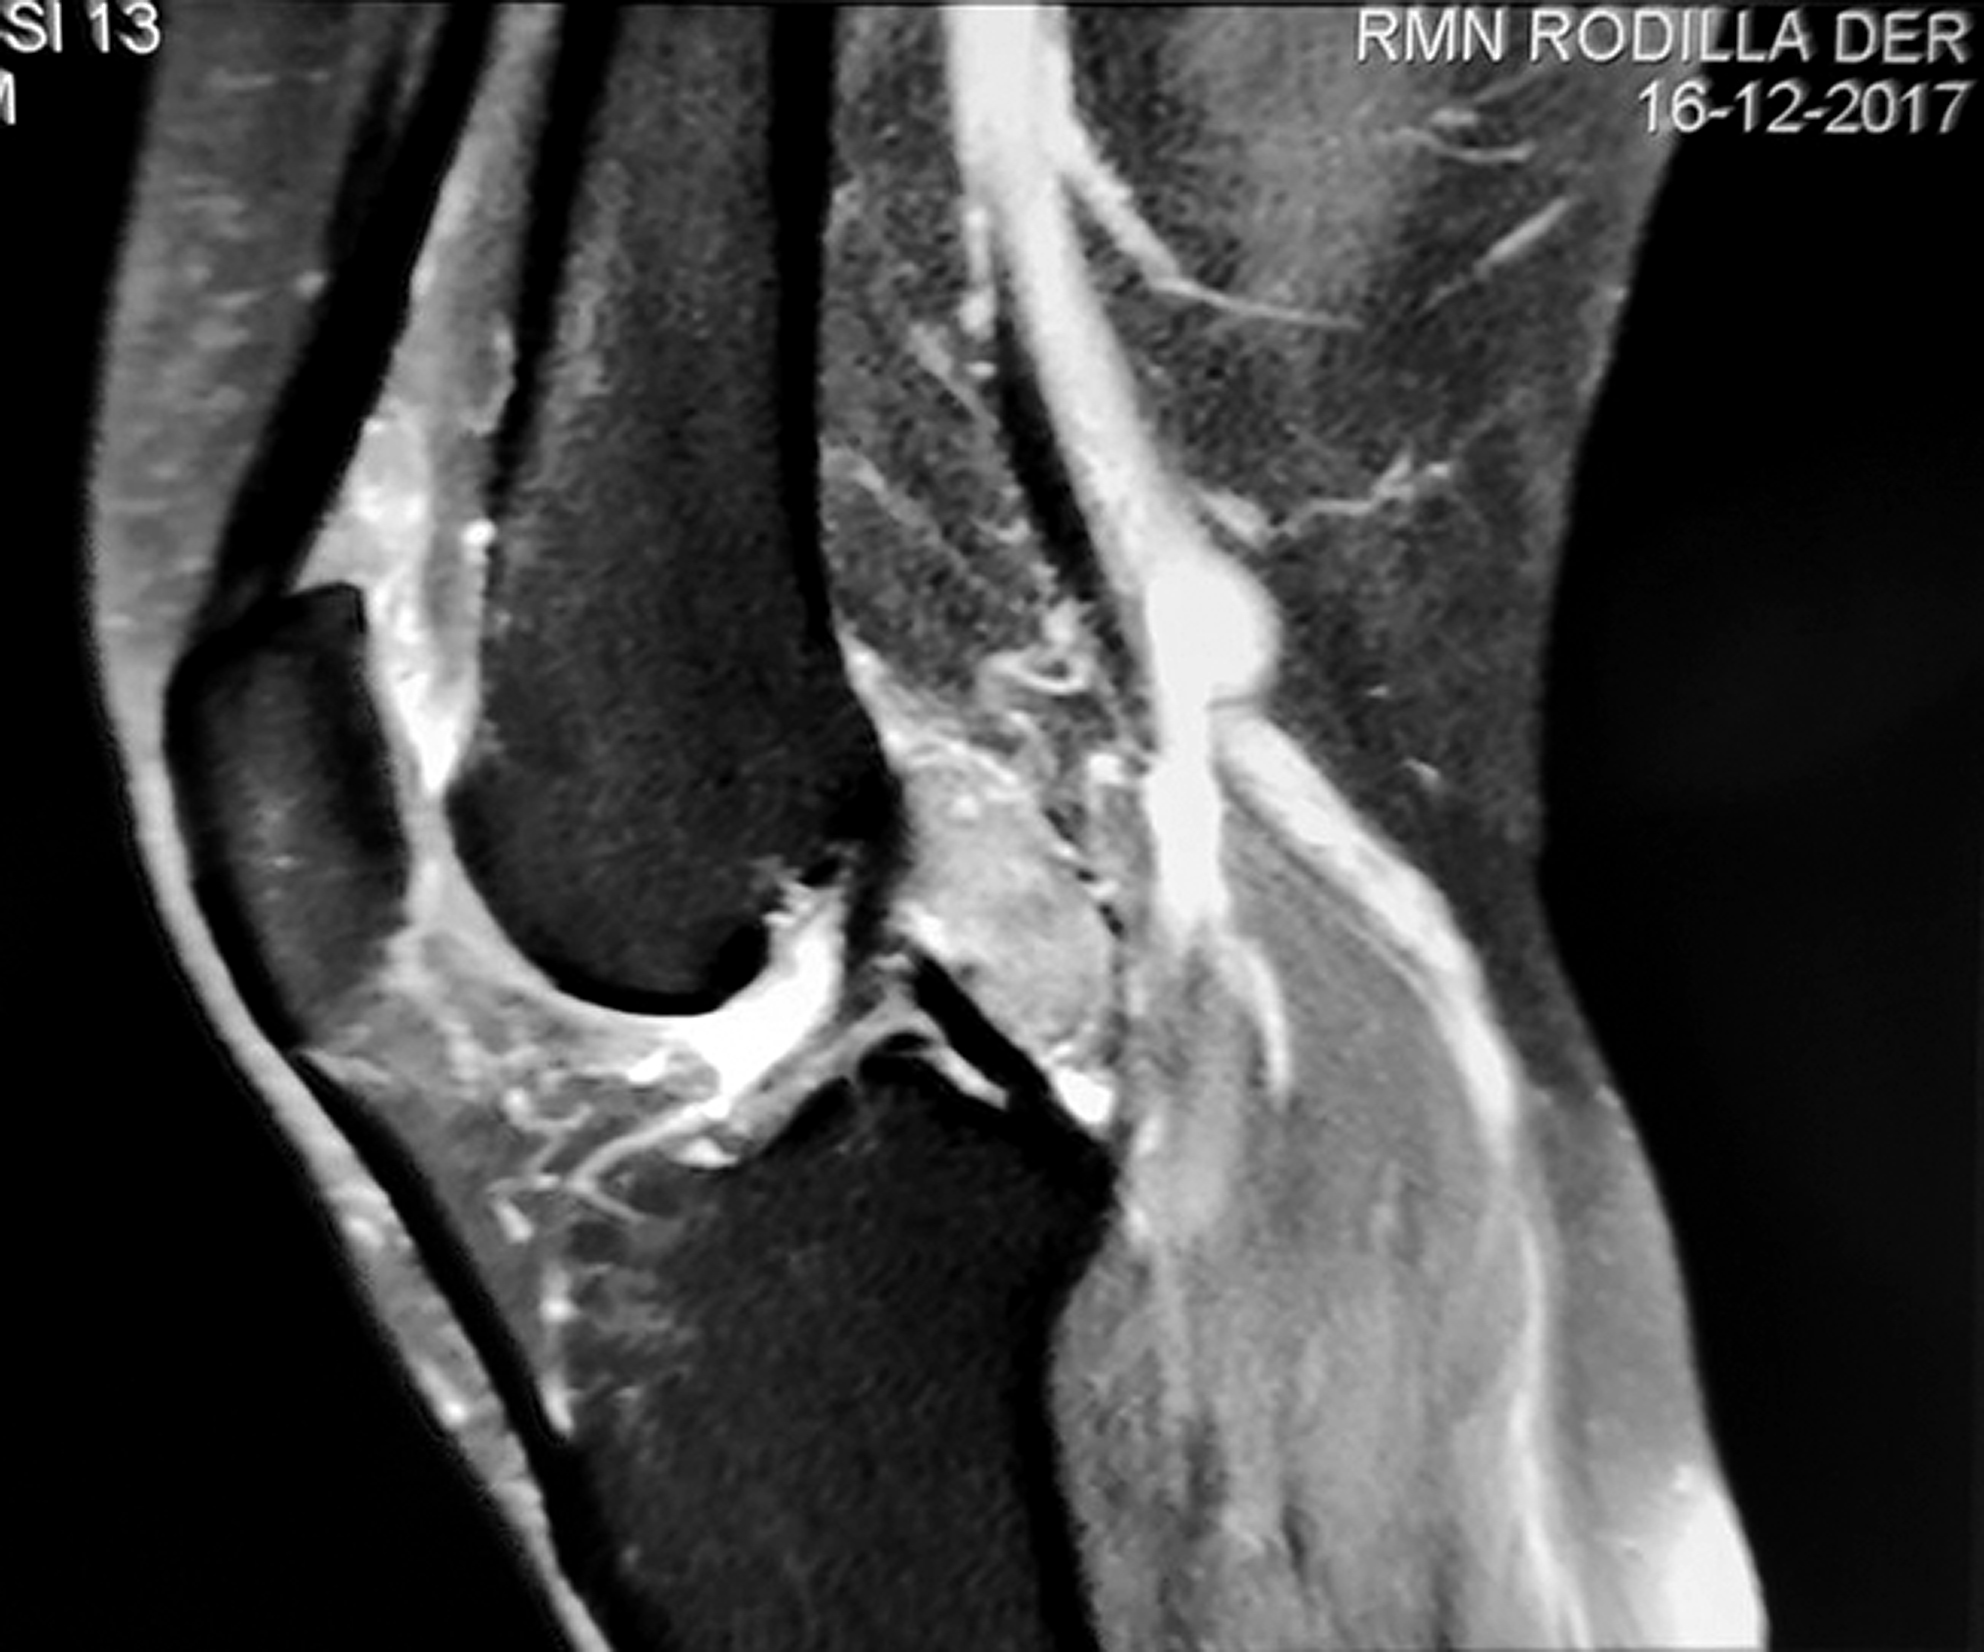

Paciente de 46 años de edad de sexo femenino consulta por dolor de rodilla derecha de dos meses de evolución, asociada a aumento de volumen, con limitación progresiva de la capacidad de realizar actividades cotidiana con episodio de bloqueo articular que resolvió espontáneamente. Al examen físico, se observa limitación de la extensión completa de 10º asociada a marcha claudicante. A la palpación se constata una pequeña masa tumoral en hueco poplíteo, dolorosa, duroelástica adherida a planos profundos. Se solicitó RMN donde se observa una masa heterogénea en T1 y T2 de naturaleza intraarticular localizada en intercóndilo posterior de la rodilla (figs. 1 y 2). Se planteó como diagnóstico diferencial sinovitis vellonodular pigmentaria o tumor tenosinovial de células gigantes. Por protocolo de servicio y para ir a la cirugía definitiva con diagnostico de certeza se realizó una biopsia guiada por TAC. La histopatología confirmó nuestra segunda hipótesis diagnóstica.

Figura 1 y 2: Localización tumoral retro LCP en cortes axiales y sagitales.